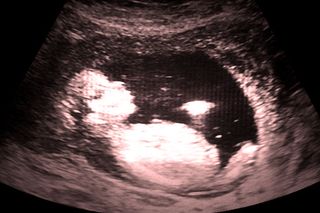

Stillbirth is a devastating complication of pregnancy that affects millions of women globally each year. It is defined as a baby born showing no signs of life where delivery occurred at or after six months (24 weeks) of pregnancy. And in the UK, 90-95% of stillbirths happen before the onset of labor.

These facts underpin the key barriers to progress. We do not have tests that reliably predict babies at high risk of stillbirth. If we did, we could use the test, deliver high-risk pregnancies early and save a life. But the tests we have do not work well. Currently an army of midwives is sent out to measure the size of the “bump”, from the pubic bone to the top of the womb, despite the fact that we know this test performs poorly in detecting poorly grown babies. Scans are normal in many women who go on to experience a stillbirth and are abnormal in many normal pregnancies, leading to intervention in healthy women who would otherwise never have had a problem.

So how do we move forward? There are three key elements. First, make sure that current patterns of care that are known to reduce stillbirth risk, such as optimizing care of pregnant women with diabetes are applied consistently. Second, learn from mistakes such as the failure to respond appropriately to risk factors, including women reporting reduced movements of a baby. Whenever a loss occurs, we should have an open and honest assessment of the care to identify any weaknesses that may have contributed to the loss. One of the ways a tragedy can be made worse is to fail to learn from them where they were potentially avoidable. Third, better methods of screening women and identifying and managing high-risk pregnancies must be developed. This is a focus of research in Cambridge, and we recently reported on combining ultrasound scans with blood tests to identify high-risk women.